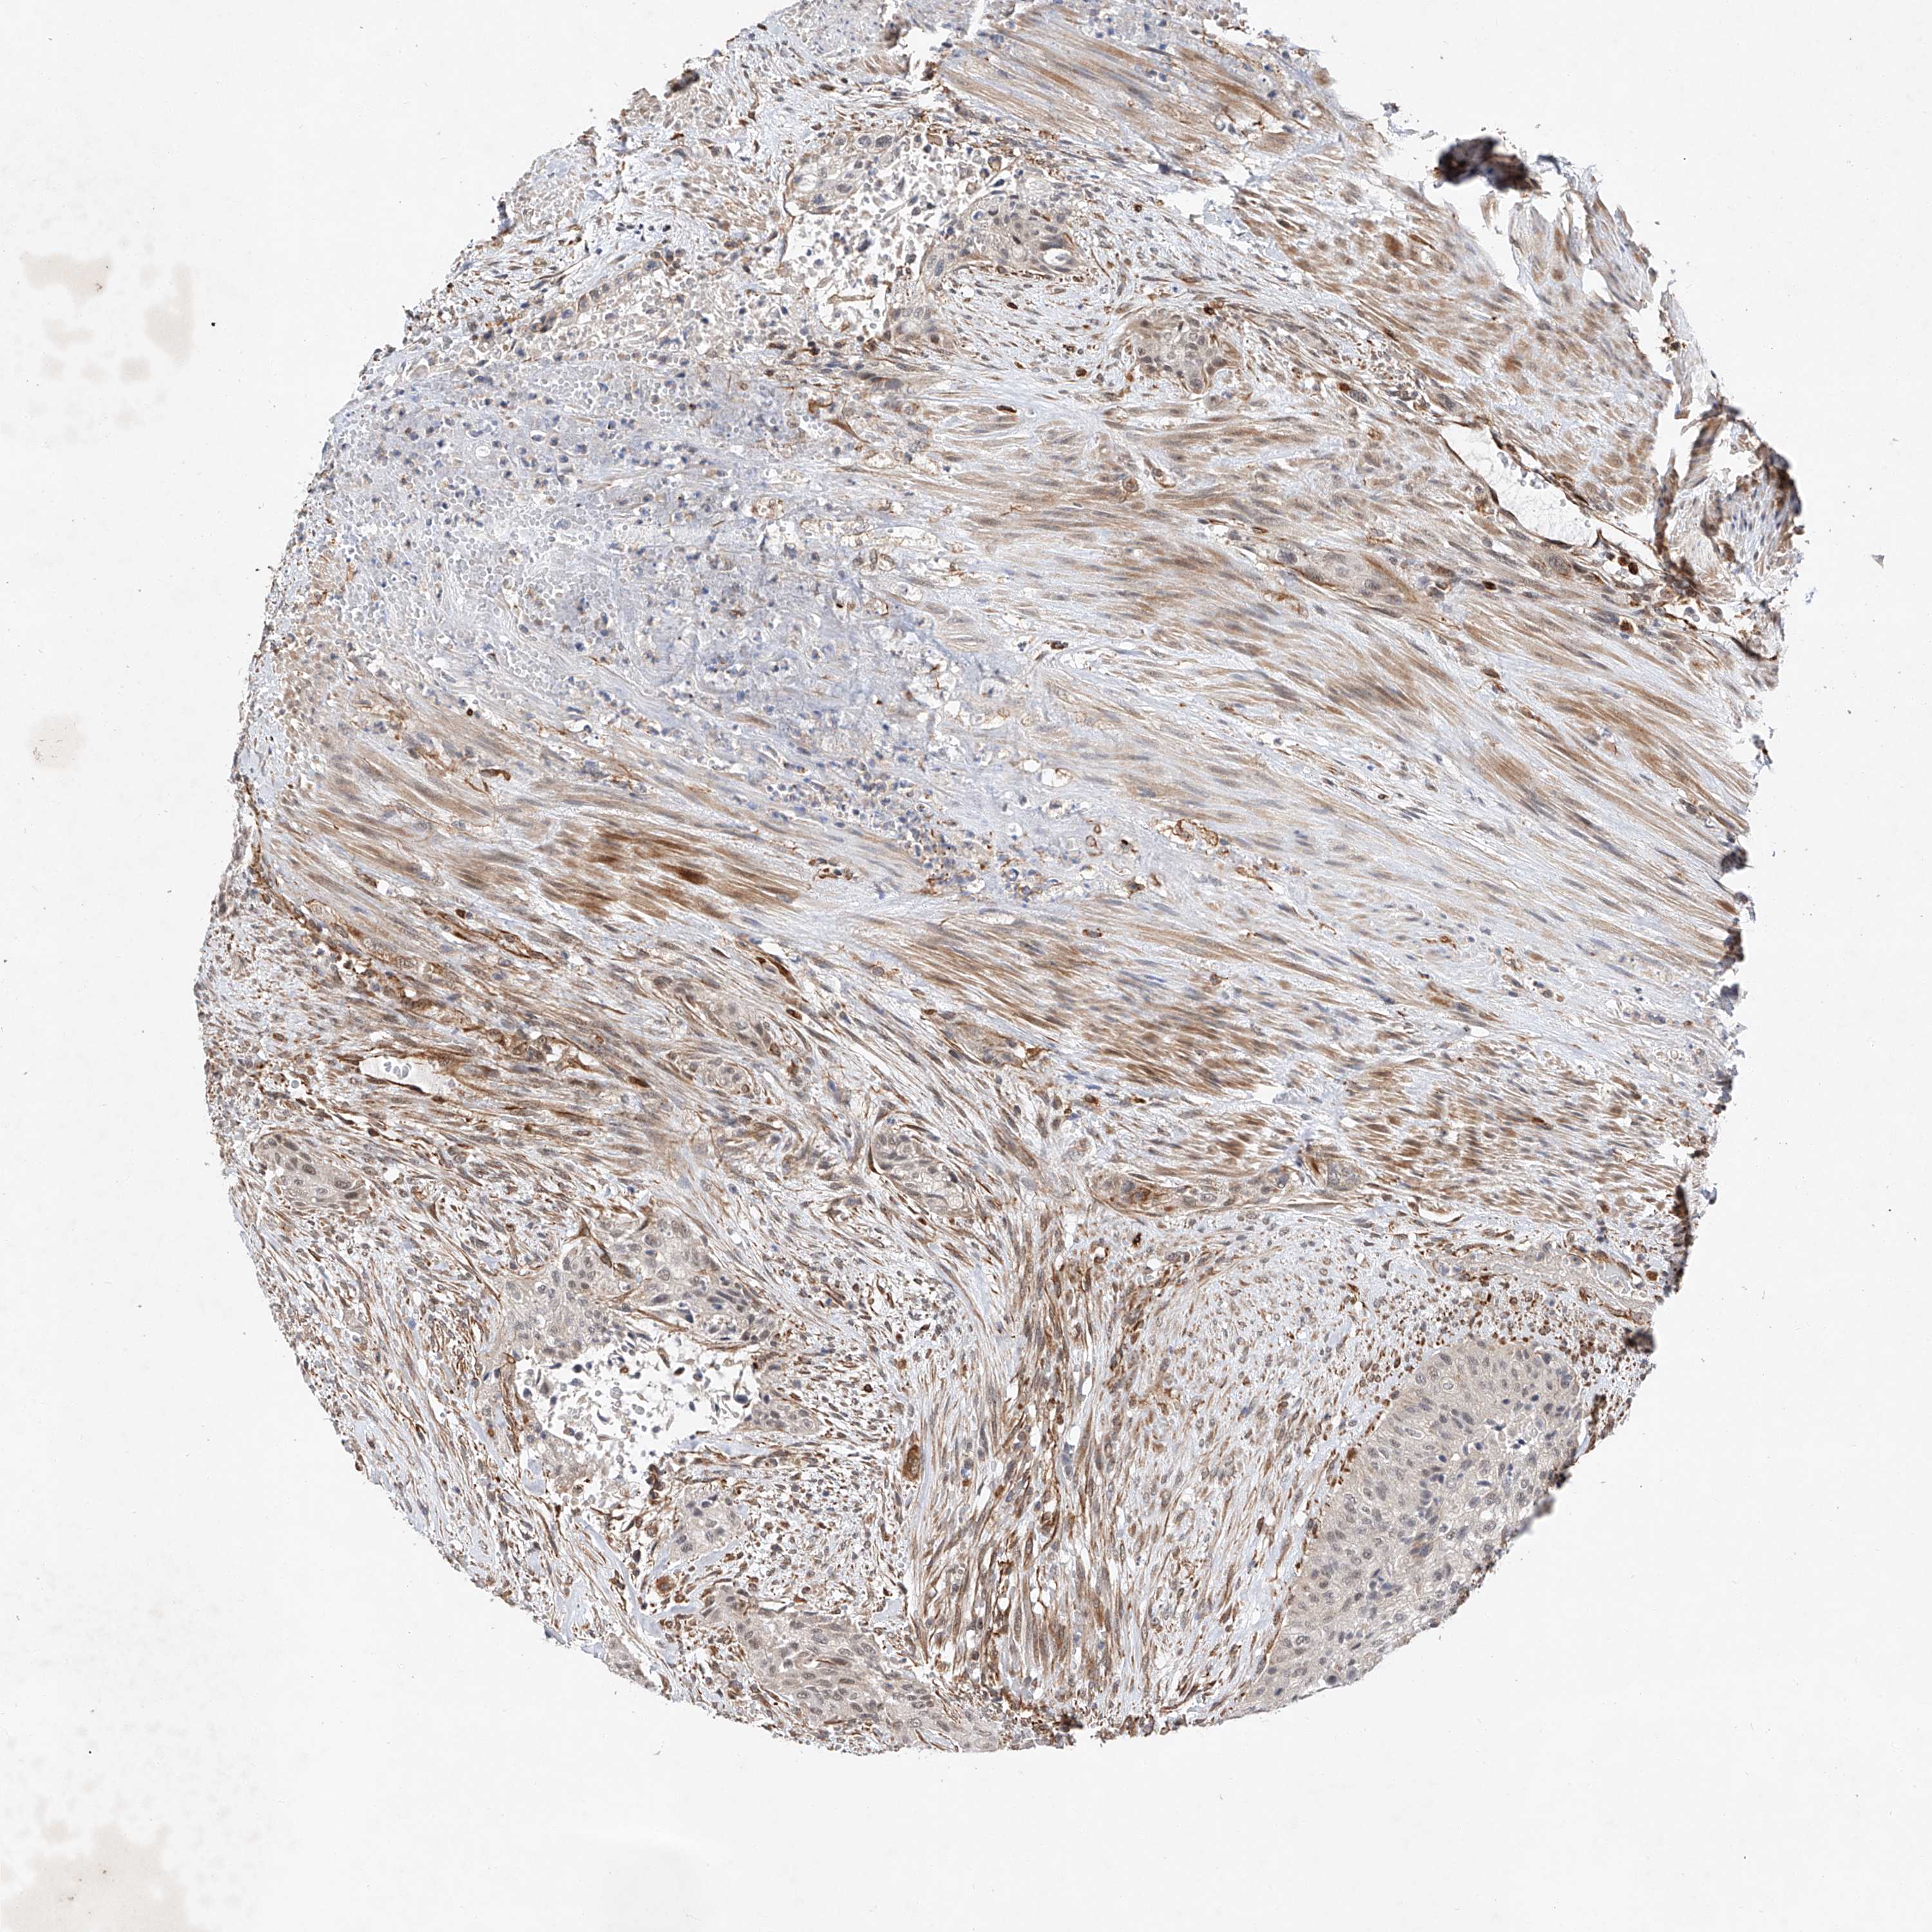

UROTHELIAL CANCER - Protein expressioni

A mouse-over function shows sample information and annotation data. Click on an image to view it in a full screen mode. Samples can be filtered based on level of antibody staining by selecting one or several of the following categories: high, medium, low and not detected. The assay and annotation is described here.

Antibody stainingi

Antibody staining in the annotated cell types in the current human tissue is reported as not detected, low, medium, or high, based on conventional immunohistochemistry profiling in selected tissues. This score is based on the combination of the staining intensity and fraction of stained cells.

Each image is clickable and will lead to virtual microscopy that enables deeper exploration of all samples and also displays staining intensity scores, fraction scores and subcellular localization as well as patient and tissue information for each sample.

Antibody HPA029281

Antibody HPA029282

Staining

High

Medium

Low

Not detected

Intensity

Strong

Moderate

Weak

Negative

Quantity

>75%

75%-25%

<25%

None

Location

Nuclear

Cytoplasmic/membranous

Cytoplasmic/membranous,nuclear

Urothelial carcinoma, Low grade

Urothelial carcinoma, High grade